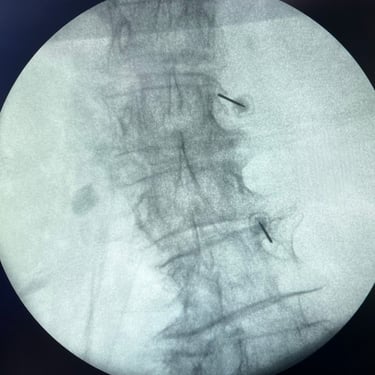

🧠 Artrodesis Lumbar Percutánea | Fijación mínimamente invasiva.

La artrodesis lumbar percutánea estabiliza la columna mediante tornillos y barras colocados por pequeñas incisiones, con mínima agresión muscular. Indicada en inestabilidad, fracturas o listesis, ofrece menor dolor postoperatorio, menor sangrado y recuperación más rápida. Es una técnica eficaz y segura para mejorar la función y calidad de vida.